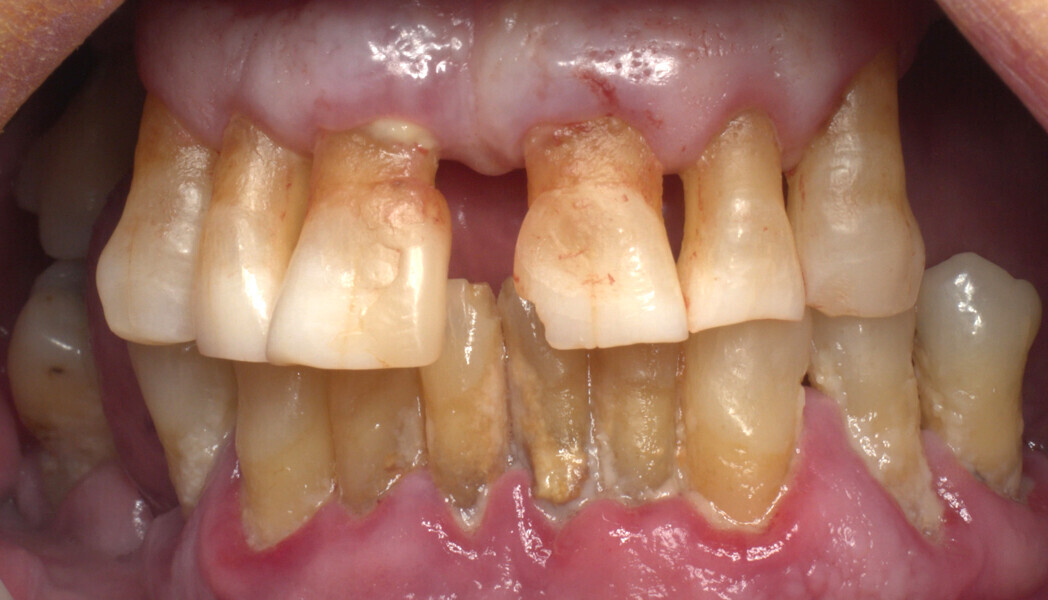

The fully digital Pro Arch protocol